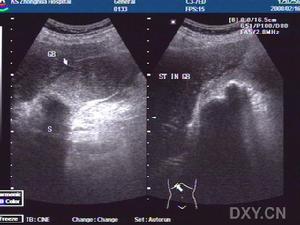

急性膽囊炎--B超當醫生檢查病人的腹部時,可以發現右上腹部有壓痛,並有腹肌緊張,大約在1/3的病人中還能摸到腫大的膽囊。化驗病人的血液,會發現多數人血中的白細胞計數及中性白細胞增多。B超檢查可發現膽囊腫大、囊壁增厚,並可見結石堵在膽囊的頸部。

3.B型超聲檢查,膽囊增大,囊壁增厚,可能可看到結石的影像。

3.B超檢查示膽囊增大,壁厚>3.5mm,內有強光團伴聲影。